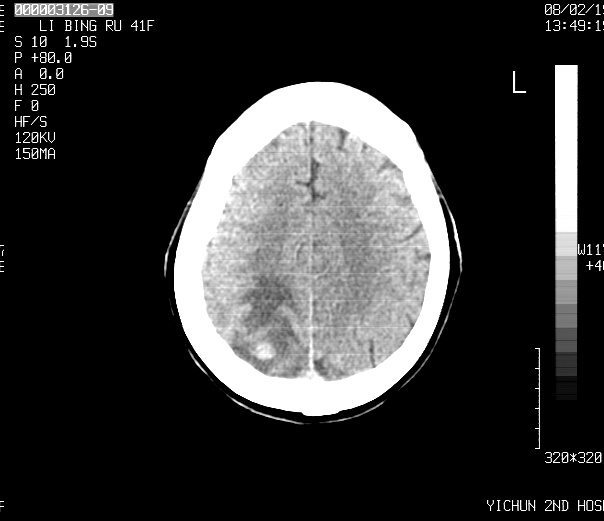

标题: CT11766:女 66岁,请会诊

请各位老师会诊

脑转移瘤

小病灶,大水肿,支持转移瘤。

首先考虑转移瘤!先查个胸部。

多发的占位病变---以小病灶,大水肿为特点,支持转移瘤